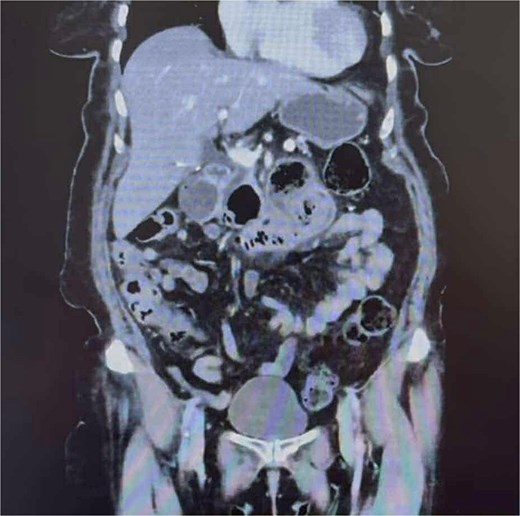

On arrival to the Emergency Department, the patient was hypertensive, however, all other vitals were within normal limits. On examination, the patient was dehydrated and focally tender in the epigastrium without peritonism. Laboratory results showed a mildly elevated white cell count of 11.4 × 109/L and a normal lactate of 1.7. Computer tomography (CT) imaging (Fig. 1) demonstrated a partially obstructing intraluminal lesion at the duodeno-jejunal junction, adjacent to an inflamed duodenal diverticulum raising suspicion for an impacted food bolus, a mass lesion or intussusception. There was no evidence of perforation, free gas or fluid.

CT abdomen and pelvis demonstrating a partially obstructing intraluminal lesion at the duodeno-jejunal junction, adjacent to an inflamed duodenal diverticulum raising suspicion for an impacted food bolus, a mass lesion or intussusception. There was no evidence of perforation, free gas, or fluid.